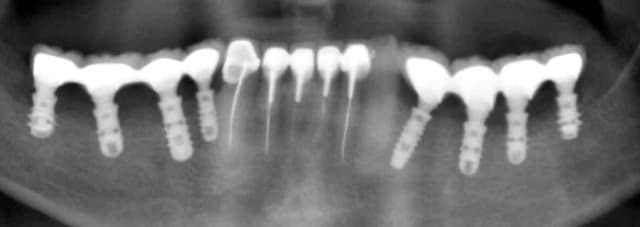

Simplement pour dire que ça peut se faire! Depuis 2 ans environ. Ok c'est au maxillaire et le bas pour l'occlusion on peut mieux faire mais chaque chose en son temps.

Moins de recul 1 an seulement pour le bas. En haut c'est une sorte de MCI avec provioire (made in drmarcus).

Maintenant si tu penses que la largeur va tu peux te baser sur cet exemple.